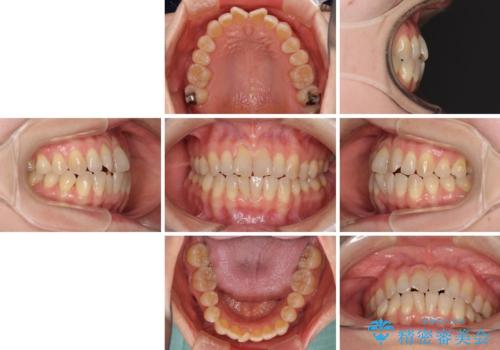

前歯の叢生と切端咬合 インビザラインによる矯正治療

- 前歯のデコボコを気にして来院された患者様です。

上下前歯の先端同士が接触する切端咬合であったため、上顎は歯列を拡大し、下顎はIPR(歯と歯の間を削る)により叢生を解消しながら歯列を小さくすることとしました。

治療前から歯肉退縮が認められ、矯正治療により悪化する可能性が考えられたため、無理のない歯の移動と頻繁な経過観察を行いました。

切端咬合はスムーズに解消され、前歯の負担を軽減させることができました。